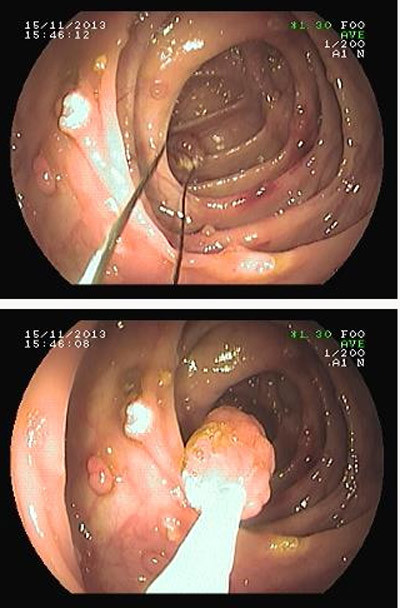

| Các khối u lành nằm rải rác trong ruột già và đang được cắt bỏ qua nội soi ruột già (ảnh chụp trực tiếp qua máy nội soi- BS Lưu Phương). |

Tại Phòng nội soi tiêu hóa, BV Nguyễn Tri Phương, với phương pháp nội soi ruột già từ đường hậu môn lên, chúng tôi đã tiến hành cắt thành công gần 40 (36 - 37) cái polyp (u lành) ở ruột già cho bệnh nhân mà không cần phẫu thuật.